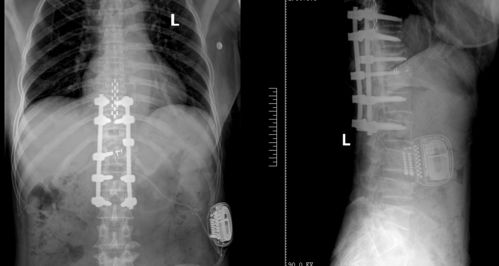

脊髓电刺激器,一种精密的医疗设备,通过植入患者脊髓附近,释放微弱的电流,以干扰疼痛信号的传递,从而达到减轻或消除疼痛的效果。这种治疗方法特别适用于那些对传统药物治疗反应不佳的患者。

在一名女性患者的案例中,脊髓电刺激疗法显示出了其卓越的效果。在接受了脊髓电刺激治疗后,患者的疼痛感明显减轻,生活质量得到了极大的提升。这一成功案例不仅为患者带来了实质性的帮助,甘肃省第二人民医院疼痛科成功实施首例脊髓电刺激植入术也为其他类似病情的患者提供了可行的治疗选择。